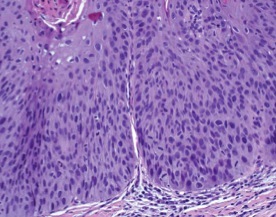

Intestinal type (LEFT IMAGE)